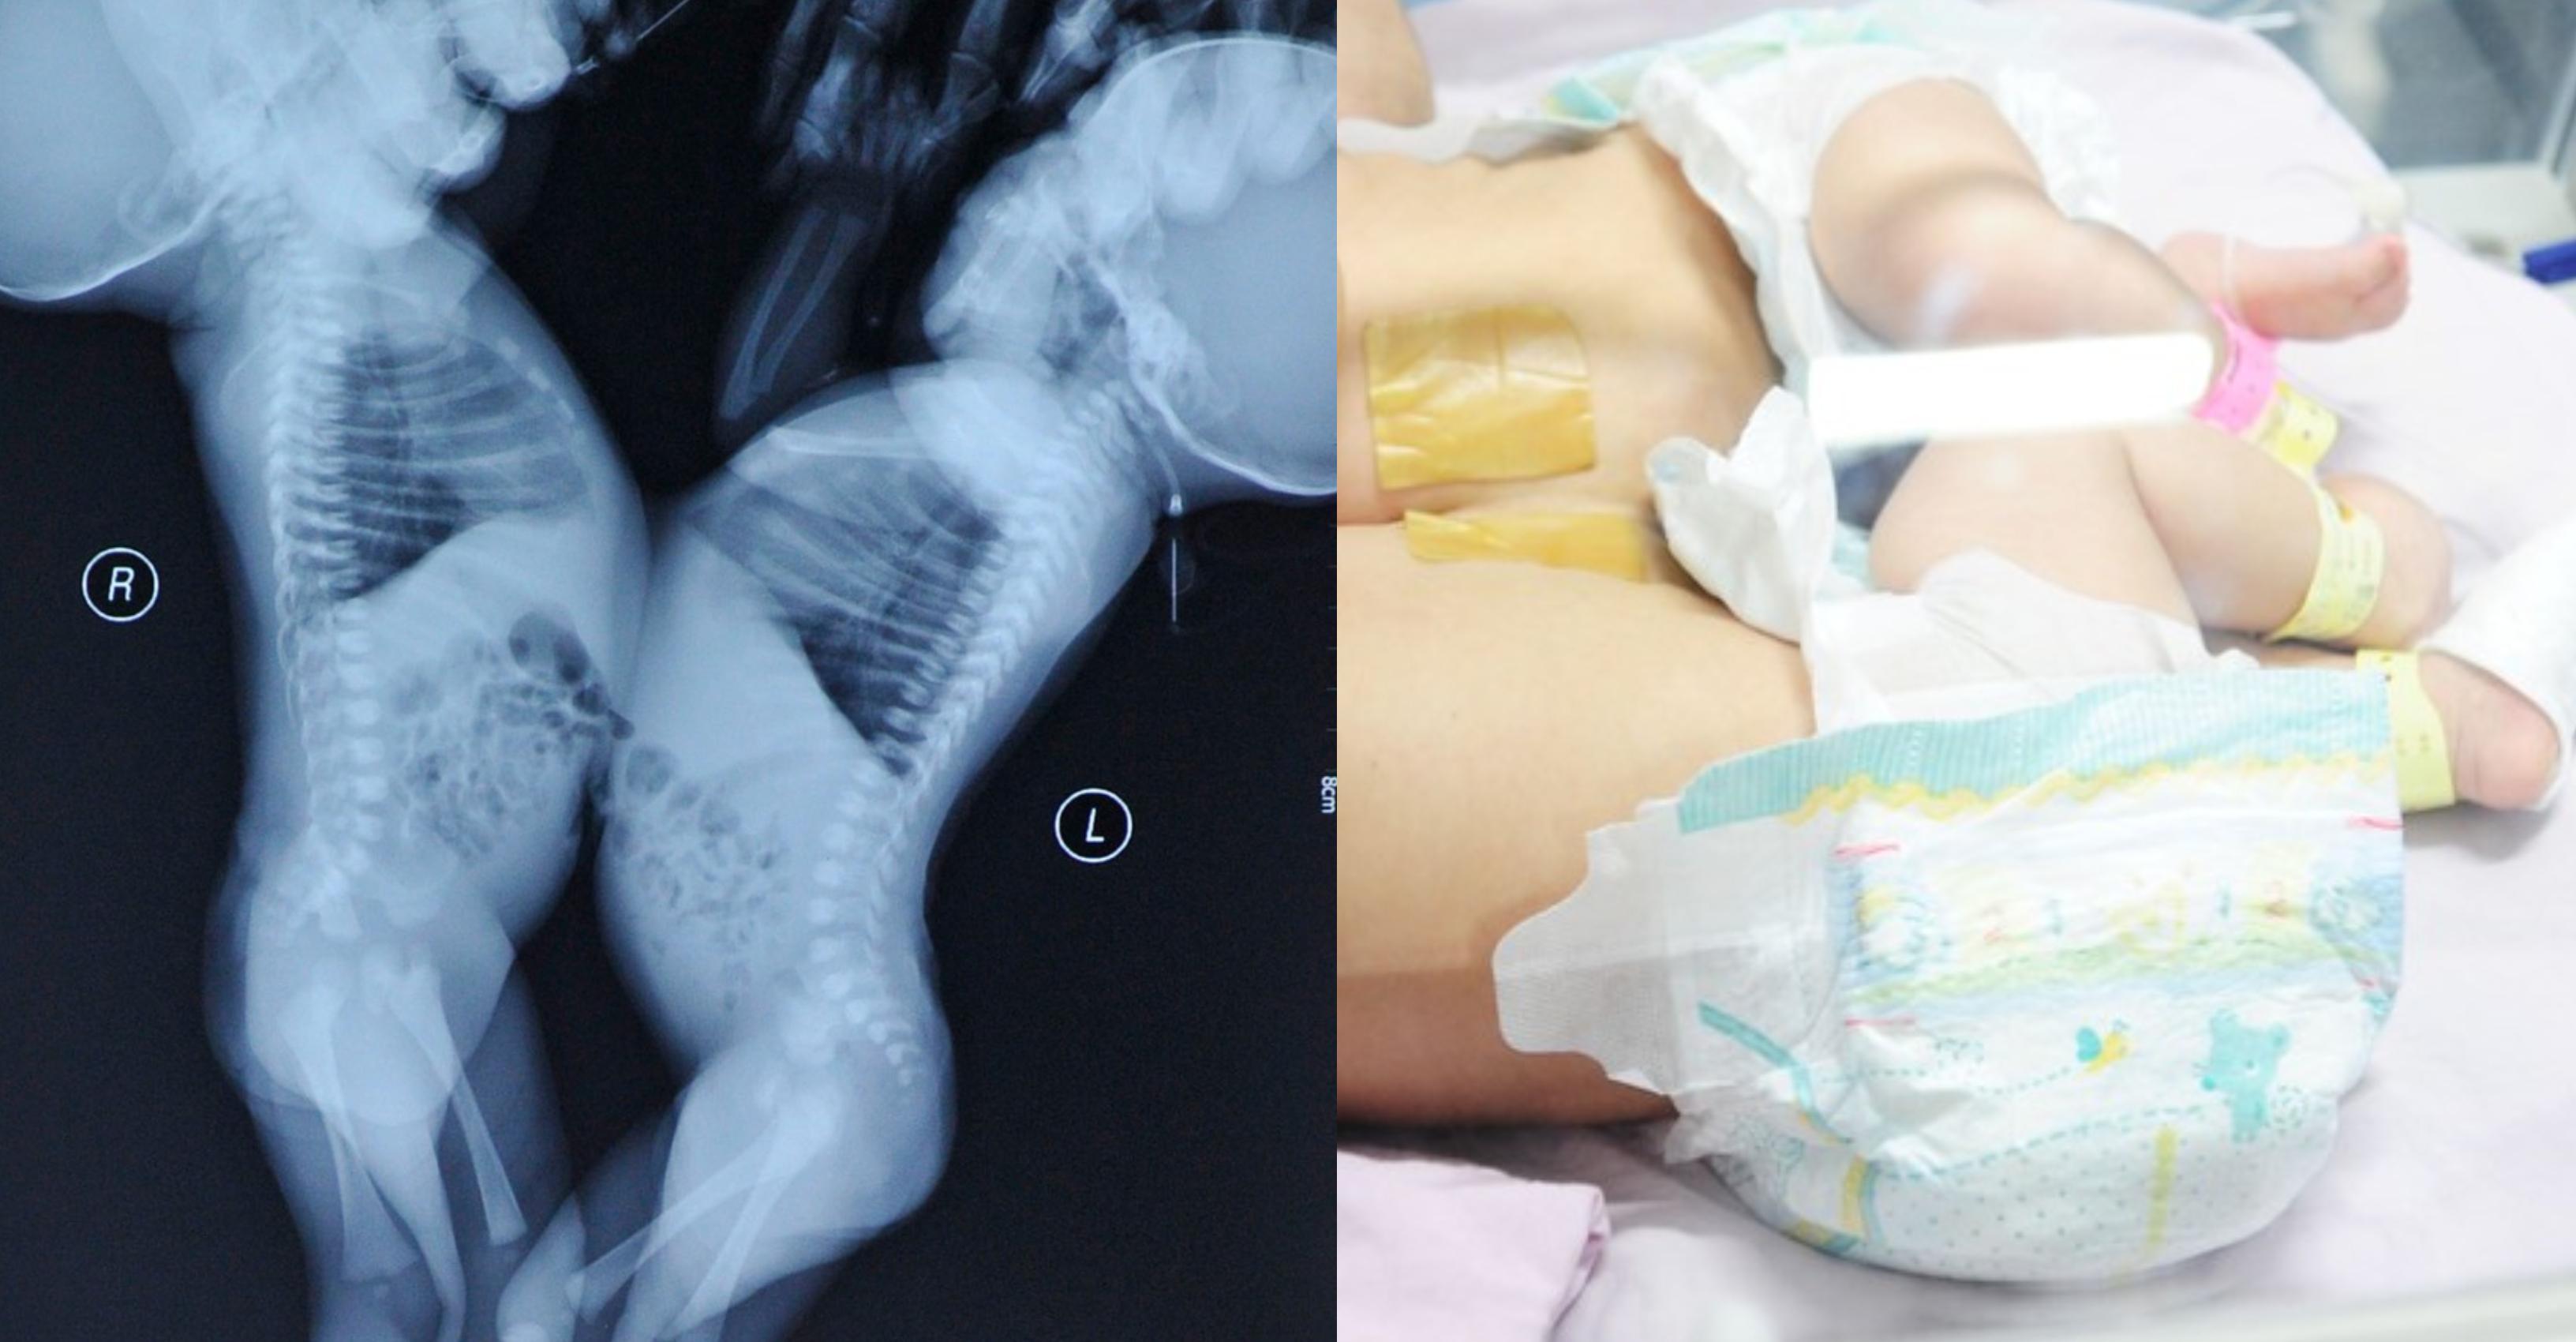

Cum s-a schimbat comportamentul a două surori siameze, după ce au fost despărțite prin operație | Imaginea 5 din 5 | Galerie Foto

S-a schimbat comportamentul a două surori siameze, după ce au fost despărțite prin operație. Cum s-a schimbat comportamentul a două surori siameze, după ce au fost despărțite prin operație Cum s-a schimbat comportamentul a două surori siameze, după ce au fost despărțite prin operație Cum s-a schimbat comportamentul a două surori siameze, după ce au fost despărțite prin operație Cum s-a schimbat comportamentul a două surori siameze, după ce au fost despărțite prin operație